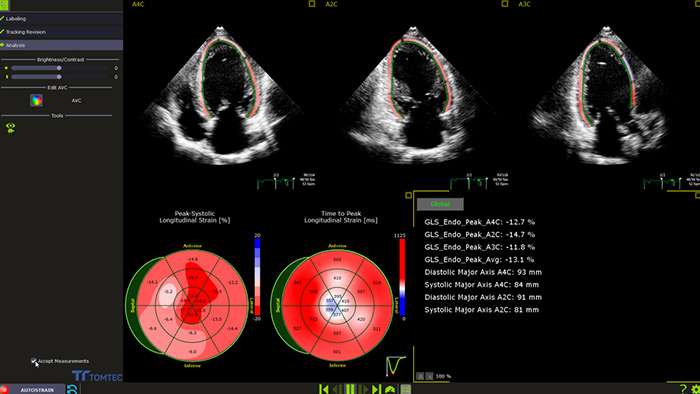

Skuteczne przeciwdziałanie kardiotoksyczności leków przeciwrakowych wymaga współpracy pomiędzy specjalistami kardiologami a onkologami. W idealnych warunkach pacjent, który ma otrzymać potencjalnie kardiotoksyczny lek, powinien przejść wstępną ocenę funkcji serca4. Należy jednak pamiętać, że proste i szeroko dostępne dwuwymiarowe badanie echokardiograficzne frakcji wyrzutowej lewej komory (LVEF) często nie pozwala na wykrycie drobnych zmian w jej kurczliwości. Bardziej dokładne pomiary zapewnia echokardiografia 3D, jednak dopiero pomiar globalnego odkształcenia wzdłużnego (GLS), który umożliwia przeprowadzenie analizy, pozwala w optymalny sposób wykryć na wczesnym etapie subkliniczne zaburzenia pracy lewej komory4.

Automatyczny pomiar GLS możliwy do wykonania podczas rutynowych badań

Aplikacja AutoStrain — dostępna w ultrasonografie lub stacji roboczej na potrzeby post-processingu — zapewnia szybki i prosty pomiar GLS dzięki funkcjom Auto View Recognition i Auto Contour Placement. „Wyszkolona” na ponad 6000 obrazów zapewnia uzyskiwanie wiarygodnych i powtarzalnych pomiarów odkształcenia lewej komory, które można wykonywać także w trakcie rutynowych badań.